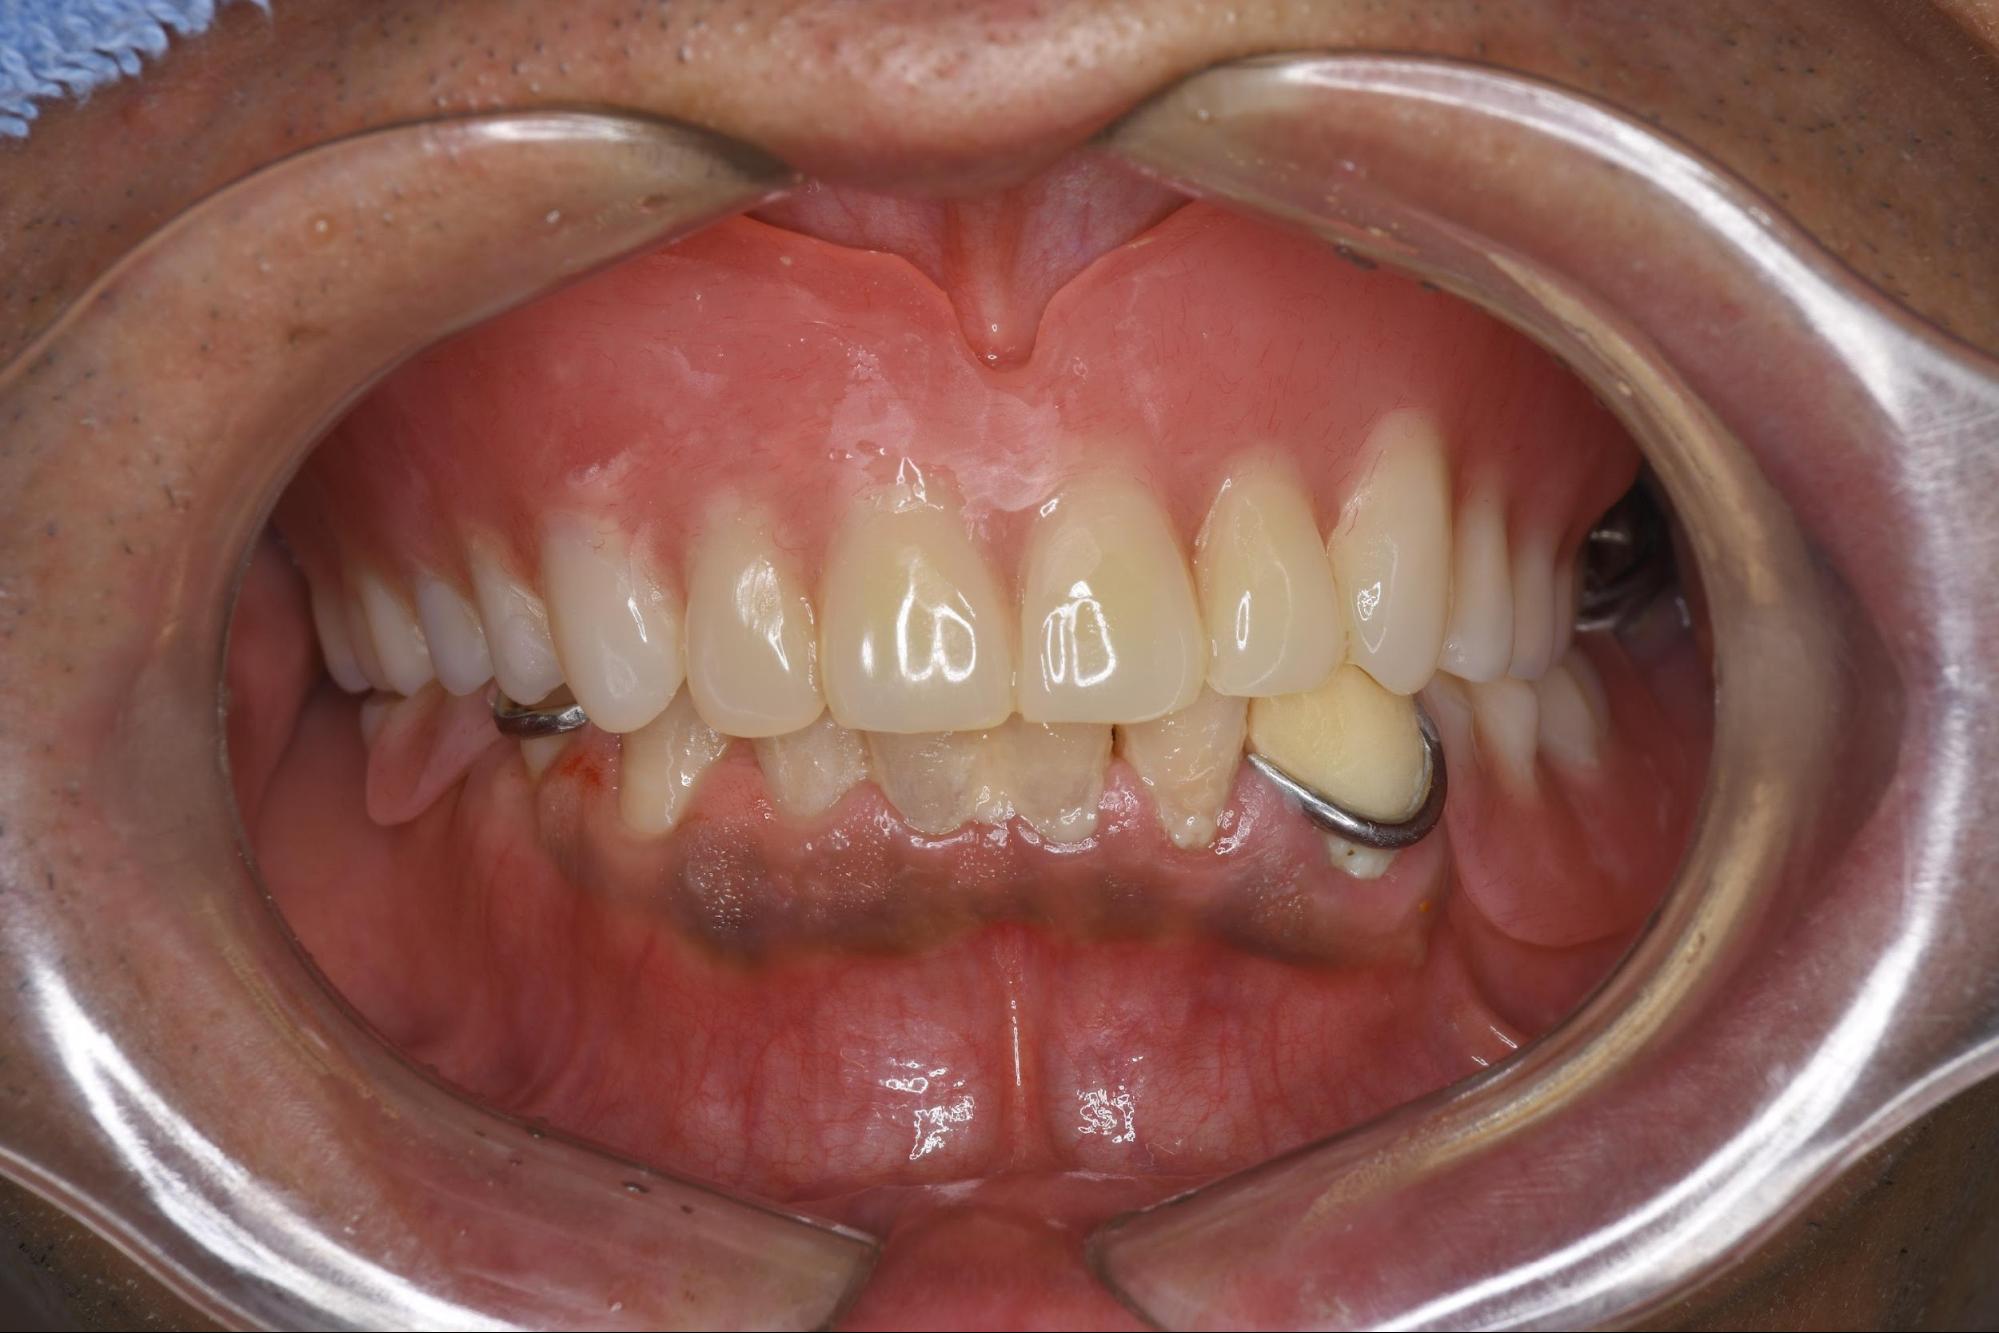

初診時症例画像

2. ご来院時の状態と診断

まず、患者さんの現在のお口の中の状態を正確に把握するため、各種精密検査を行いました。 パノラマレントゲン撮影、歯周病の進行度を測る精密検査に加え、インプラント治療の診断には不可欠となる、顎の骨の立体的な状態(厚みや高さ、神経の位置など)を把握するための歯科用3D-CT撮影を行いました。

検査の結果、残念ながら上顎(うわあご)には、重度の歯周病によって骨が溶けてグラグラになってしまった歯や、根が割れてしまっている歯(歯根破折)が多数認められました。 これらの歯を保存することは極めて困難であり、抜歯が必要な状態でした。

残すことができる歯の本数も非常に少なく、健康保険適応のブリッジ治療(失った歯の両隣の歯を削って橋渡しする治療)も適応外と診断されました。 他の医院で言われた通り、治療の選択肢としては「取り外し式の入れ歯」か、外科処置を伴う「インプラント治療」かの二択となる、非常に難しい状況であることが再確認されました。